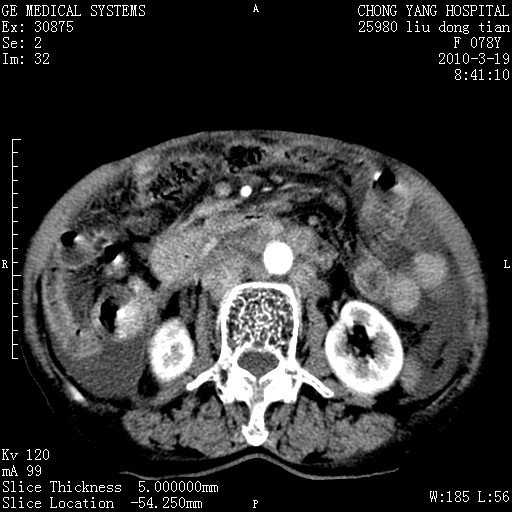

标题: CT25199:F 78Y 腹胀半年 消瘦乏力 [打印本页]

胆囊壁增厚并明显强化,胆囊癌伴多发转移瘤可能性大,淋巴瘤不除外,右肾囊肿,胸腹水.

考虑nhl,肝、脾、腹膜腔及腹膜后多发淋巴结受侵,腹水,右肾囊肿,慢性胆囊炎,右侧少量胸腔积液。

胰头有肿块形成,胰头ca伴肝脾、腹膜腹膜后转移

胆囊有软组织影有强化,支持胆囊癌,肝脾、腹膜后淋巴结转移。

nhl的淋巴结多围绕主动脉,而且主动脉会移位,所以不考虑nhl。

分开来讲:肝左叶、尾叶病灶有不均强化像肝癌;

脾脏病灶无强化,像多发囊肿或淋巴管瘤,不除外淋巴瘤(低强化);

胆囊增生性病变:胆囊癌,腺肌增生症,慢性胆囊炎;

肝门、胰腺头、腹膜后多个团块: 淋巴瘤,转移;

腔静脉肝内段细小有无布加可能?

一元论最好了 淋巴瘤所致改变; 胆囊癌转移不像,胆囊周围肝组织清晰,肝癌淋巴结转移?三元论都不止。

胰头ca伴肝脾、腹膜腹膜后转移!

最后报的胰头癌多发转移,脾脏单独考虑囊肿或淋巴管瘤。